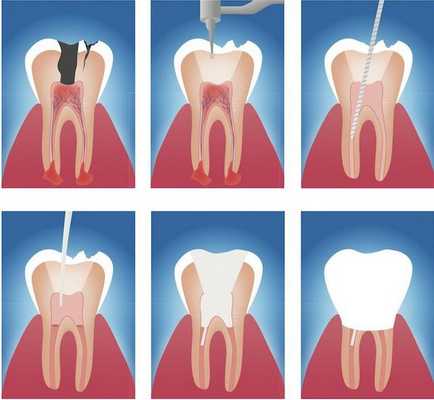

Лечение любой формы апикального периодонтита проводится в несколько посещений и включает в себя три основных этапа:

- Механическую подготовку. На первом этапе под местной анестезией производится вскрытие пораженного зуба и очистка полости от остатков погибшей пульпы и кариозных тканей, после чего осуществляется обработка и расширение корневых каналов – создаются условия для оттока экссудата.

- Антисептическую обработку. Для дезинфекции каналов часто применяется ультразвуковая терапия. В дальнейшем в область корня зуба помещаются противовоспалительные и антибактериальные препараты в виде паст.

- Пломбирование каналов. Если воспалительный процесс в периодонте удалось купировать, на заключительном этапе лечения проводят тщательное пломбирование корневых каналов с последующим рентгенологическим контролем качества. При успешности манипуляций, лечение завершается установкой постоянной пломбы, а в случае сильного разрушения зуба его закрывают коронкой.

Этапы эндодонтического лечения:

- адекватное обезболивание;

- изоляция зуба или нескольких зубов, в которых будут проводится манипуляции, от полости рта;

- создание эндодонтического доступа (иссечение твёрдых тканей зуба или пломбировочного материала, закрывающих доступ в систему корневого канала;

- прохождение и определение длинны корневого канала (это длинна от устья до верхушки корня);

- создание корневого канала определённого диаметра и формы;

- введение в корневой канал лекарственных препаратов;

- пломбирование корневого канала;

- восстановление анатомии и функции зуба с помощью пломбировочного материала или ортопедической конструкции.